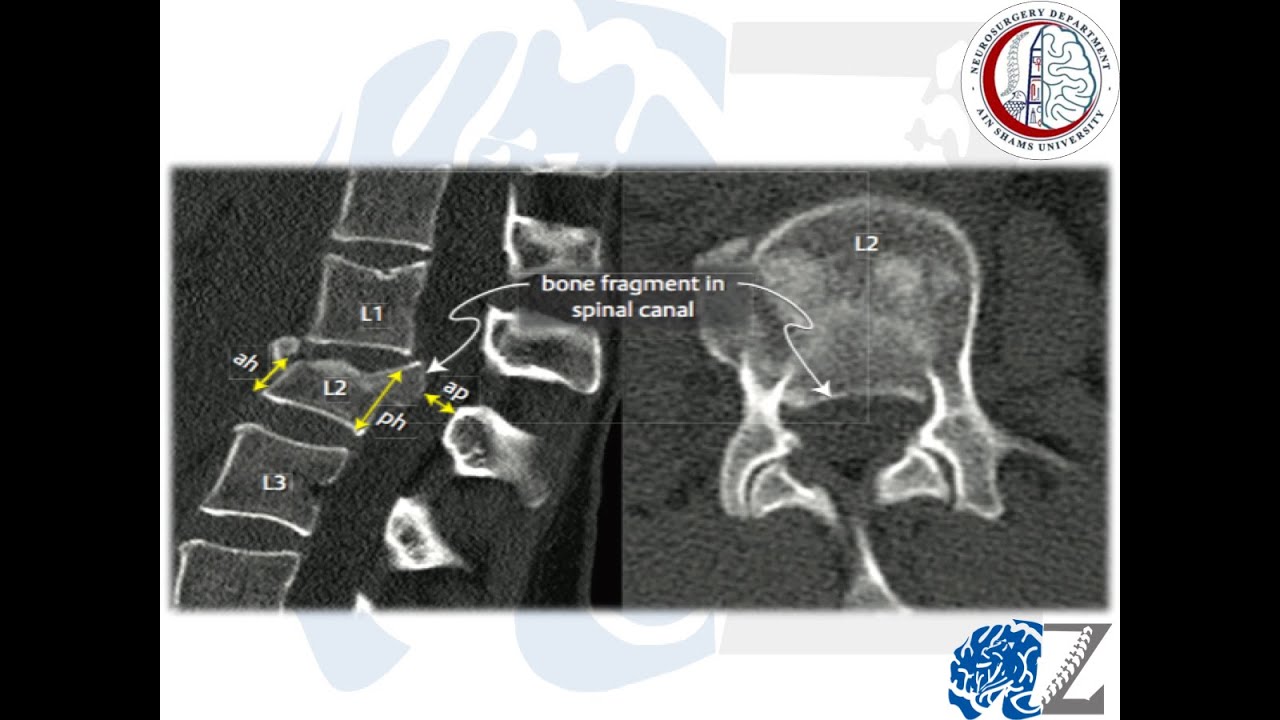

Spine Trauma (23):  Thoraco-Lumbar Spine Fractures (8) : Management of Burst Fractures